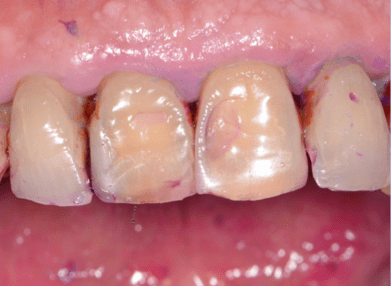

Placca batterica, sonda parodontale nella tasca, malattia parodontale o piorrea.

Alimentazione e denti saniBlog

Piorrea e alimentazione